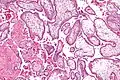

Micrograph showing chorionic villi. Intermediate magnification. H&E stain. -

Chorionic villi are villi that sprout from the chorion to provide maximal contact area with maternal blood.

They are an essential element in pregnancy from a histomorphologic perspective, and are, by definition, a product of conception. Branches of the umbilical arteries carry embryonic blood to the villi. After circulating through the capillaries of the villi, blood returns to the embryo through the umbilical vein. Thus, villi are part of the border between maternal and fetal blood during pregnancy.

The bulk of the villi consist of connective tissues that contain blood vessels. Most of the cells in the connective tissue core of the villi are fibroblasts. Macrophages known as Hofbauer cells are also present.